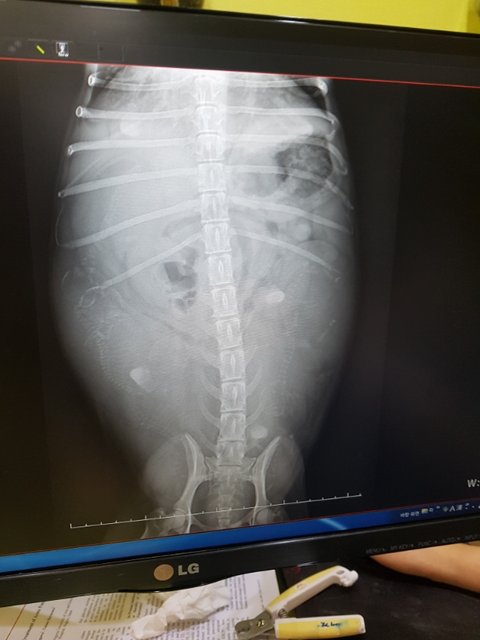

6마리의 새끼를 품은 엄마 롤라

우리 롤라가 임신이랍니다

애기가 보이는것만 6마리..

사상충치료위해 검진당시 완전초기라 보이지 않았습니다

갑자기 배가 불러왔고 혹시 복수가 찬건 아닌지 걱정했지만...